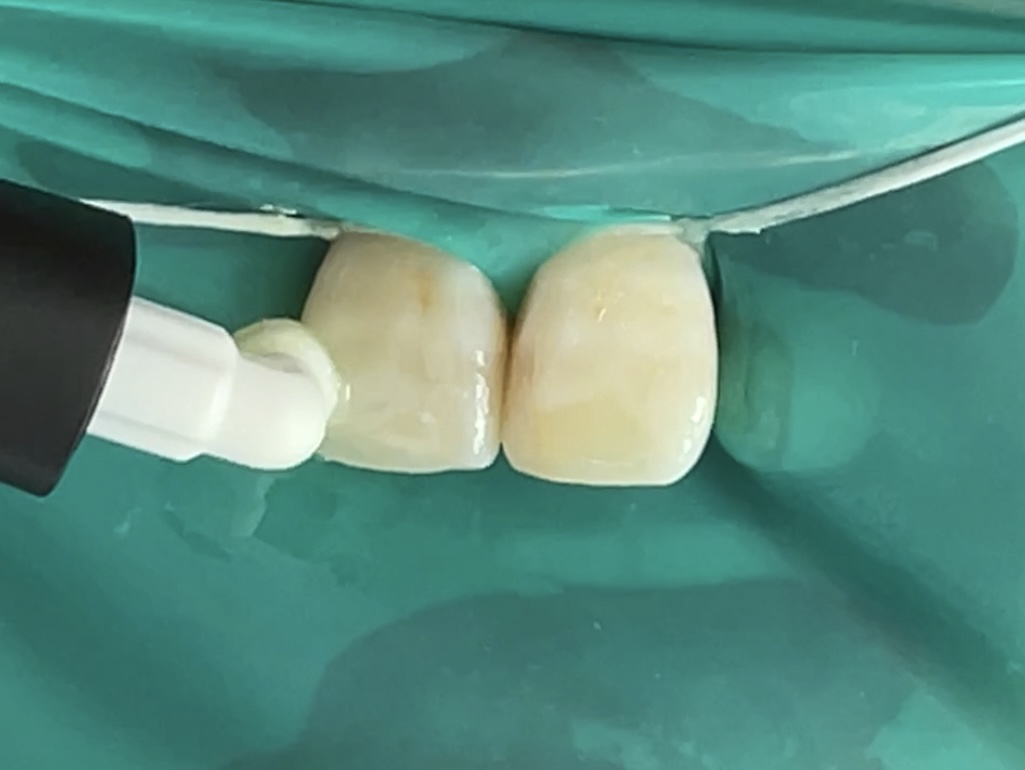

ラバーダムを装着して、治療する歯だけをお口の外にして治療をします。周囲にお薬が付いてしまったり、唾液の侵入を防いだりしながら治療を行います。ラバーダム防湿をしないと治療がうまく行かない場合があります。